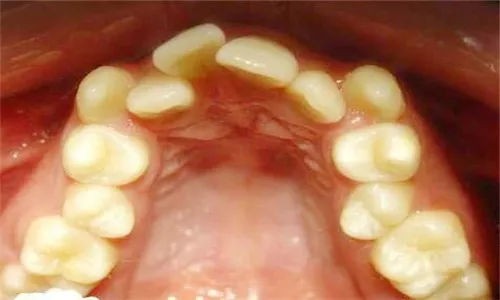

不一定哦! 部分牙列畸形的问题,是牙齿拥挤导致的,比如这样:

由于太拥挤,矫正时需要拔掉部分牙齿,给其余牙齿腾出空间。